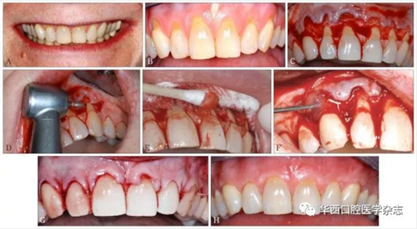

根據(jù)豬和人的釉質(zhì)蛋白高度同源的特性,科學(xué)家們從小豬胚胎中提煉出EMD[15]。EMD不但能促進(jìn)牙周膜成纖維細(xì)胞的生長(zhǎng),還可以抑制上皮細(xì)胞的生長(zhǎng)。這是一個(gè)非常重要的特征,因?yàn)樯掀さ目焖偕L(zhǎng)會(huì)與牙周膜和牙槽骨的生長(zhǎng)產(chǎn)生競(jìng)爭(zhēng),在牙周組織再生過(guò)程中,如果上皮的生長(zhǎng)占據(jù)了牙周膜和牙槽骨的再生空間,會(huì)造成牙周組織以修復(fù)結(jié)束,而沒(méi)有形成真正的牙周組織再生重建。近年來(lái),臨床醫(yī)生利用EMD再生牙周組織的特性,逐漸應(yīng)用于根面覆蓋手術(shù)[16]。研究[17]證實(shí),利用EMD結(jié)合冠向復(fù)位瓣術(shù)治療牙齦退縮,根面覆蓋率與游離結(jié)締組織結(jié)合冠向復(fù)位瓣術(shù)基本相同。EMD和冠向復(fù)位瓣術(shù)結(jié)合,不但較單做冠向復(fù)位瓣術(shù)牙根覆蓋率高,而且明顯增加了附著齦的寬度[18]。具體手術(shù)方法見圖3。

A:患者中等高“微笑線”,但可見明顯退縮的牙齦,影響美觀;B:從左側(cè)上頜尖牙到右側(cè)上頜尖牙,牙齦廣泛進(jìn)行性退縮,根面敏感,臨床附著水平和附著齦喪失;C:上頜從左側(cè)尖牙到右側(cè)尖牙翻起半厚瓣;D:常規(guī)根面處理,包括高速鉆進(jìn)行根面平整;E:pH為中性的24%乙二胺四乙酸處理根面;F:在縫合打結(jié)之前,將EDM注射在牙根表面上;G:無(wú)張力情況下,使用5-0可吸收線行連續(xù)褥式縫合,半厚瓣冠向復(fù)位將根面完全覆蓋;H:術(shù)后8個(gè)月基本達(dá)到完全根面覆蓋,而且角化組織(附著齦)增加了3~4 mm。

圖 3 EDM結(jié)合冠向復(fù)位瓣手術(shù)